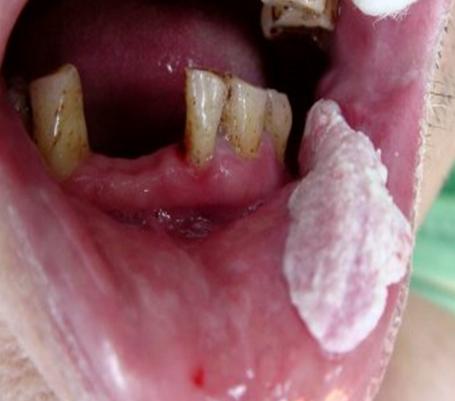

陈忠实为什么会得舌癌,陈忠实的舌癌做了什么治疗癌前病变——疣状增生↑

癌前病变是指具有潜在恶性转变可能的病变。超过两周不痊愈的慢性口腔溃疡,要警惕了,这可能是口腔癌的癌前病变。口腔癌的癌前病变还包括黏膜红斑、黏膜白斑、黏膜下纤维化、疣状增生、慢性溃疡等。癌前病变如果长期不治疗或者是刺激源一直存在,那么这样的病变转变为口腔癌的可能性就很高。例如,口腔内有尖锐蛀牙,或者残余的牙根对口腔形成慢性刺激,就有可能加大罹患口腔癌的潜在风险。

• 警惕这些癌前病变